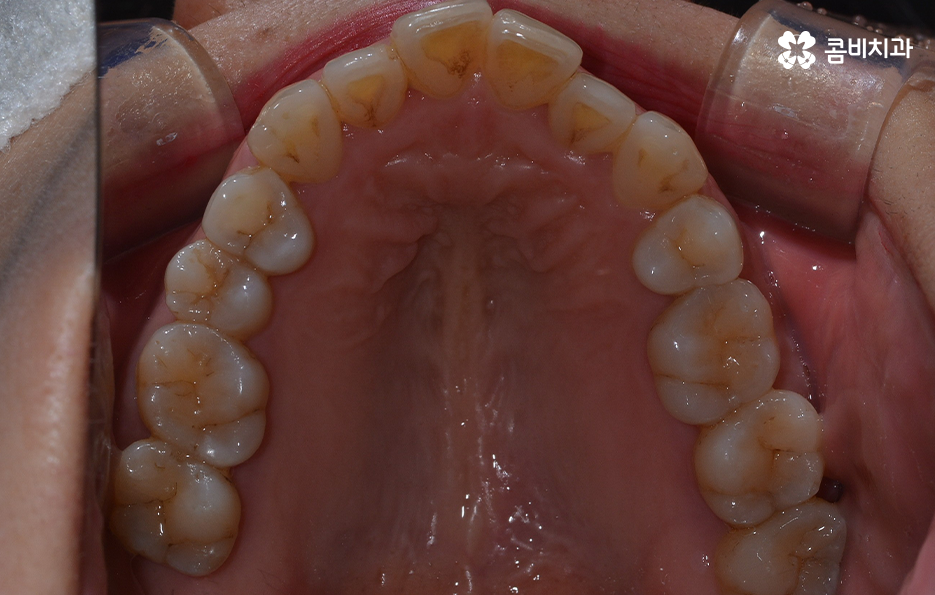

오늘 보시는 교정 사례의 경우를 보시면 아랫니의 틀어짐도 크지만 측면 사진으로 보시면 치열로 인해 돌출입에 영향을 준다는 사실도 알 수 있어요. 즉 치열과 함께 돌출입도 함께 고치고 싶어하기 때문에 치열도 재배열 하지만 치아 안쪽으로 넣어서 입술라인과 얼굴형으로 볼 때도 돌출입도 치료하는 치료 계획을 세웠기 때문에 작은 어금니 발치를 통한 치아의 이동 공간을 확보한 사례로 볼 수 있어요

치아교정의 원리를 생각하면 치아를 안쪽으로 넣어야 하는 치료 계획을 세울 때 치아가 이동할 수 있는 공간을 확보해야 하고 특히 얼굴형까지 고려하여 치아를 크게 이동시켜야 할 때는 발치 교정이 꼭 필요할 수 있는데요